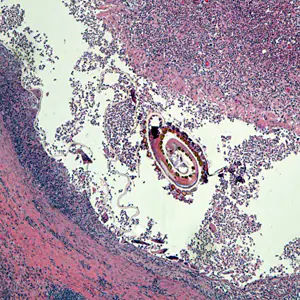

A 61- year-old man presented in 2015 with abdominal pain and was found to have a perforated sigmoid colon. Initial course notable for intra-abdominal collection, associated with the perforation, which was drained. Surgical procedures included sigmoid resection and diverting colostomy. A biopsied specimen revealed cancer and appropriate chemotherapy was administered for 7 months. No reported travel to rural areas or exposure to farm animals and only travel history outside the U.S. was to Canada and the Bahamas on a cruise 25 years ago. The patient has not eaten beef or pork for about 7 years, aside from a 2 month period in 2015 (while undergoing the cancer treatment). As an outpatient he was having carcinoembryonic antigen (CEA) levels monitored, and a recent increase prompted a positron emission tomography (PET) scan that revealed a liver lesion. He was admitted for a right liver lobe resection and a small incidental capsule nodule was noticed, removed and sent to pathology. Previous laboratory results included no evidence of eosinophilia. Figures A–F show what was observed on a hematoxylin and eosin stained section. Figures B and C were captured at 200x magnification; Figures D–F at 400x. What is your diagnosis? Based on what criteria?

Figure A